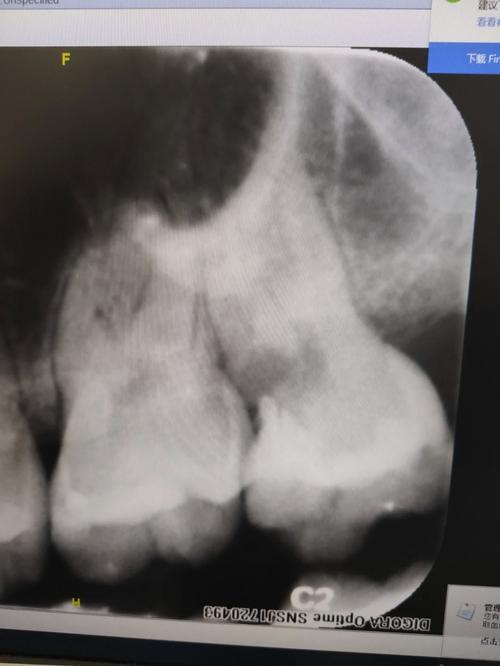

急性牙髓炎主要是由于牙髓因细菌感染而发生急性炎症,细菌产生毒素,使封闭的牙髓腔内的压力急剧增高,同时压迫牙髓产生剧烈疼痛。急性牙髓炎的疼痛具有一定的特点,一般表现为夜间痛、自发性放射性疼痛,冷热刺激痛,患者不能定位,检查时牙冠表面常可见龋洞。患者急诊就诊时可予以开髓减压,疼痛可立即缓解,...。